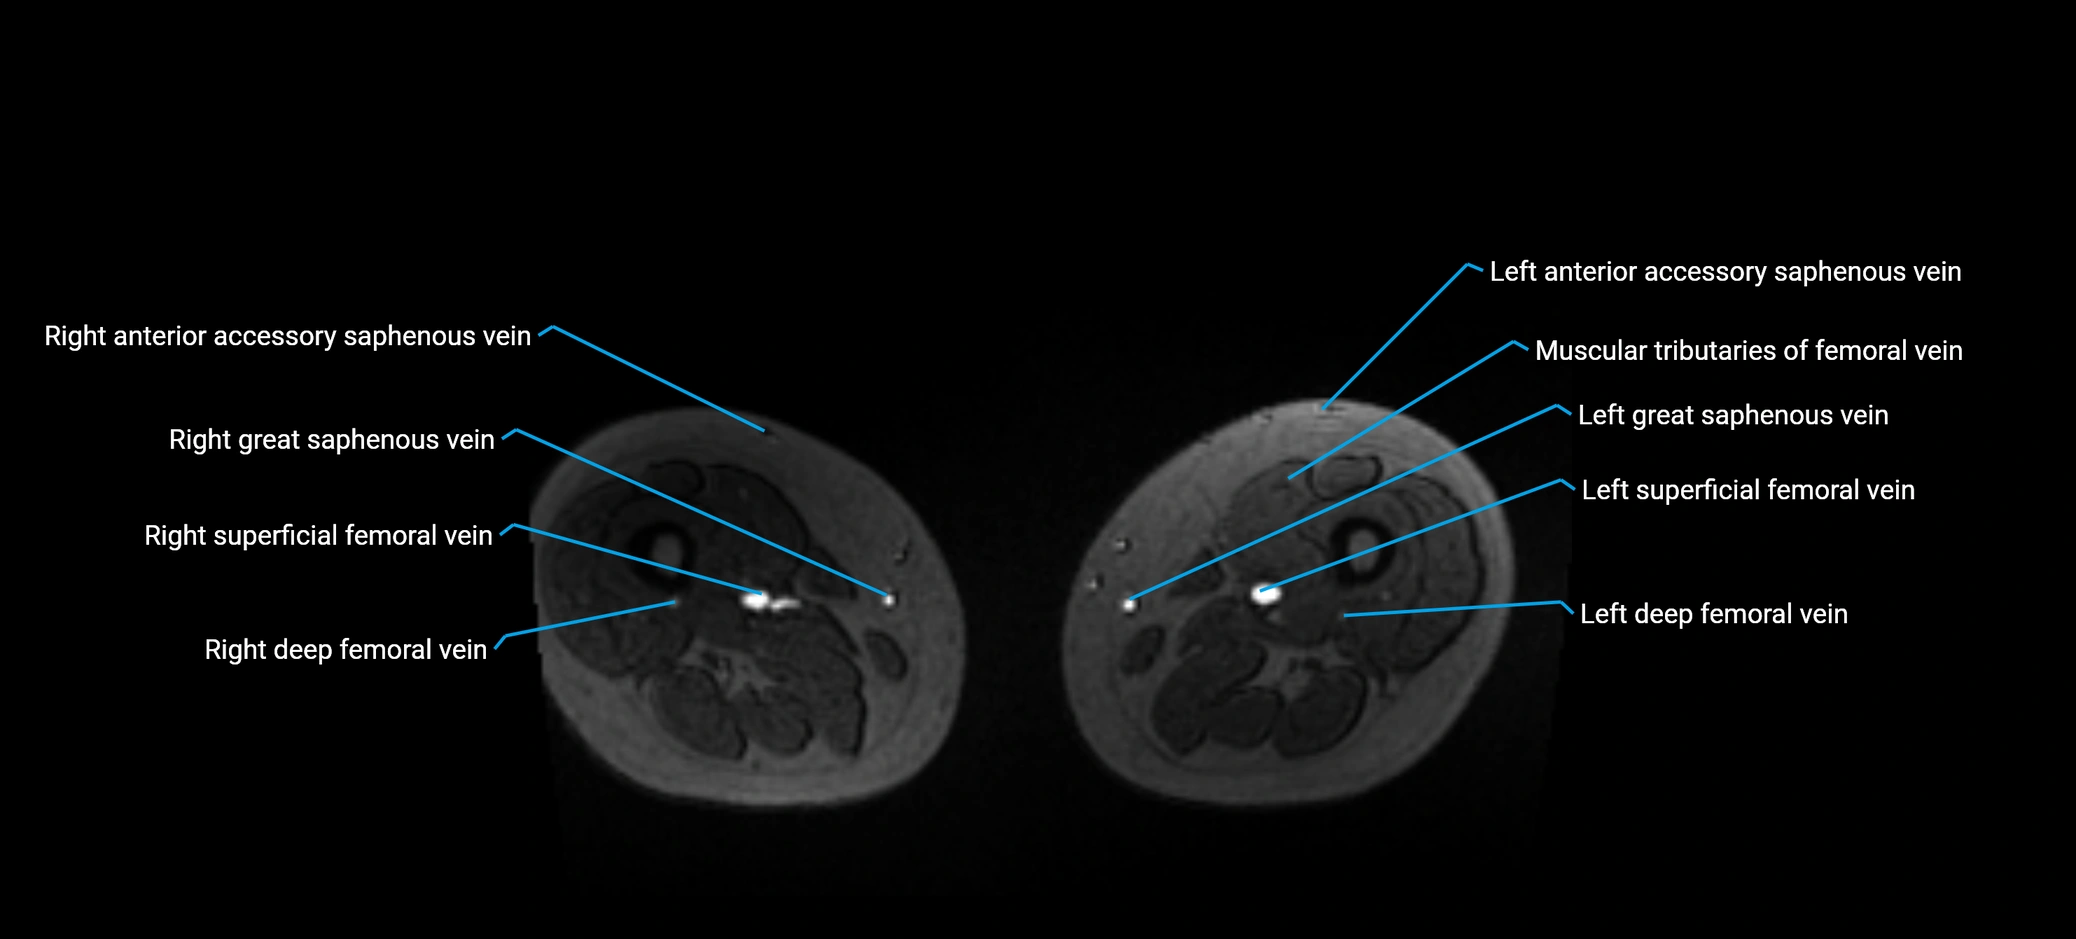

MRI image

image